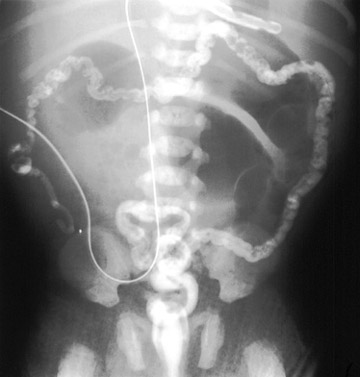

Meconium

ileus is caused by thick, tenacious meconium that adheres to the wall

of the small bowel and causes obstruction most often at the level of the

ileocecal valve in a neonate. Almost all patients with meconium ileus have cystic fibrosis;

10-15% of CF patients present with meconium ileus. Complications include

ileal atresia and/or stenosis, volvulus, perforation, and meconium peritonitis

(due to obstruction and ischemia from tenacious meconium). It can be treated nonsurgically

with water-soluble enemas to relieve the obstruction or be treated surgically.

| Multiple dilated loops of bowel and an unused microcolon on barium enema. |